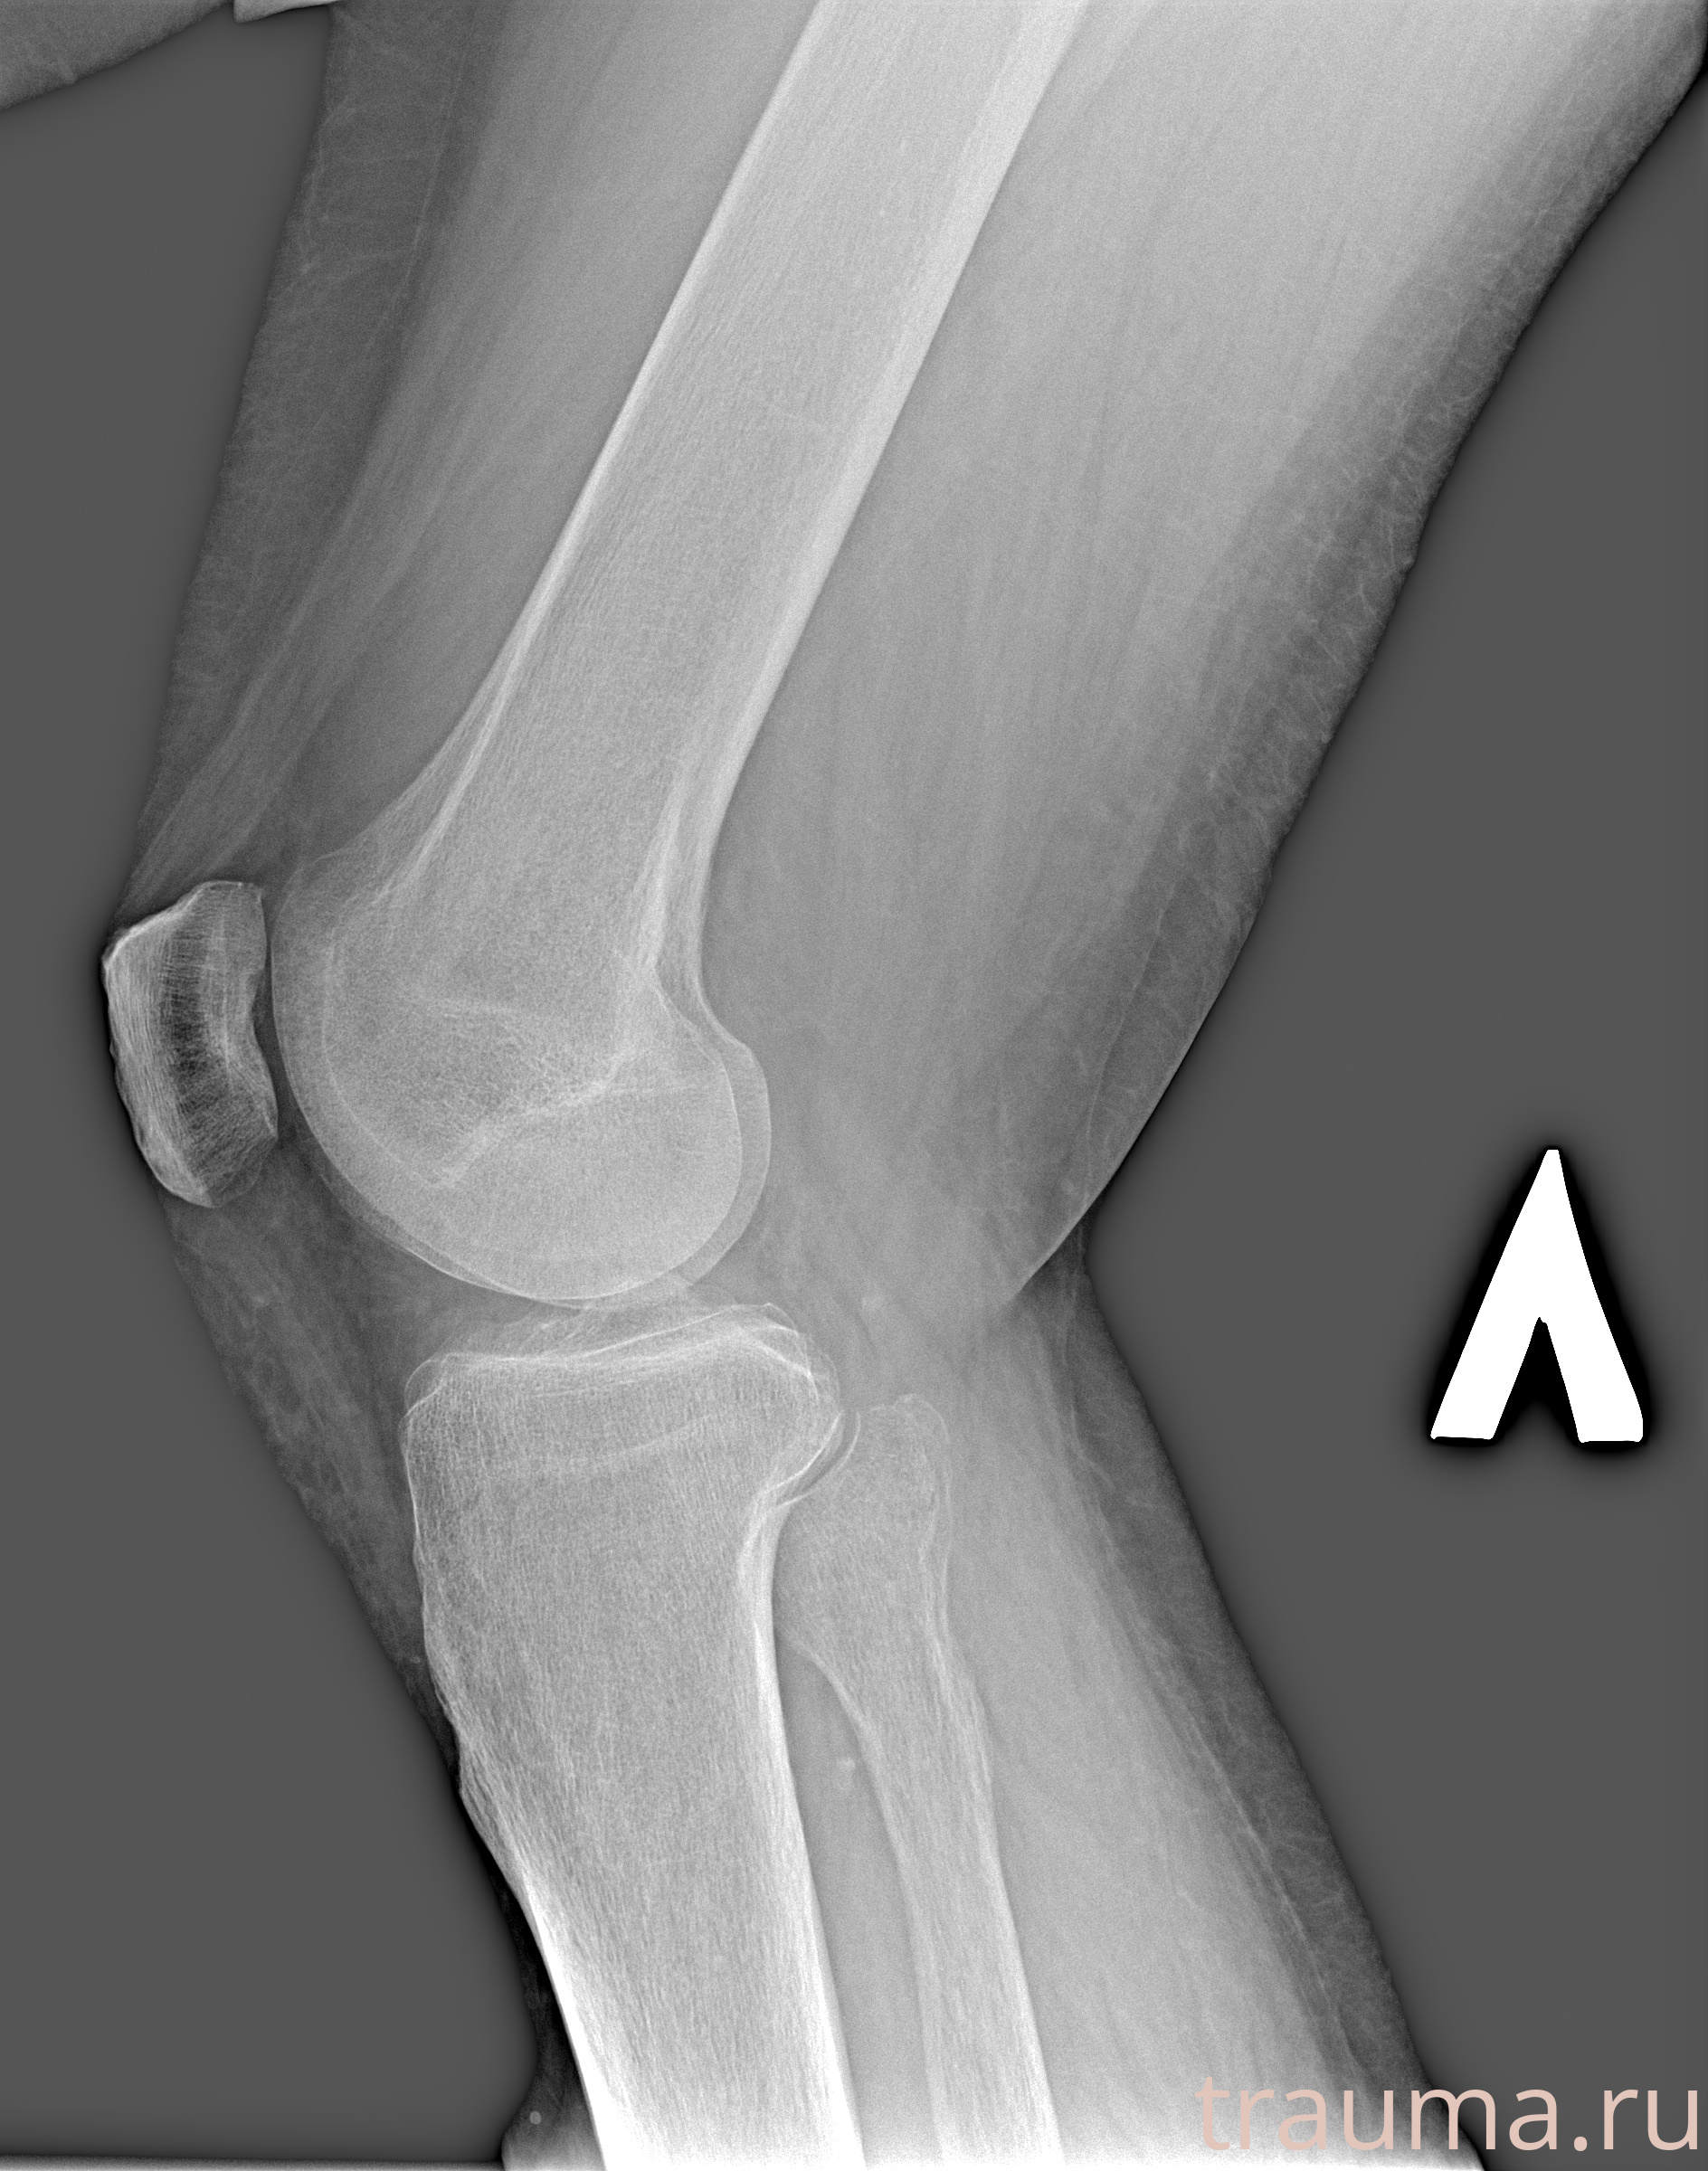

Рентгенограммы